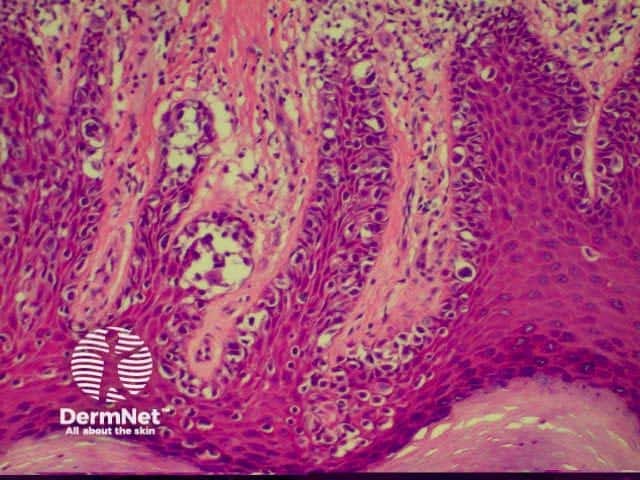

Superficial, intraepidermal or in-situ squamous cell carcinoma is also described clinically as Bowen disease and presents as a slowly growing red scaly or crusted plaque. It may arise in non-sun exposed skin as well as in sun-exposed skin. Link to a clinical description of in situ squamous cell carcinoma.

The histological features of in-situ squamous cell carcinoma show extensive overlap with actinic keratosis and are:

Pathology of in situ SCC